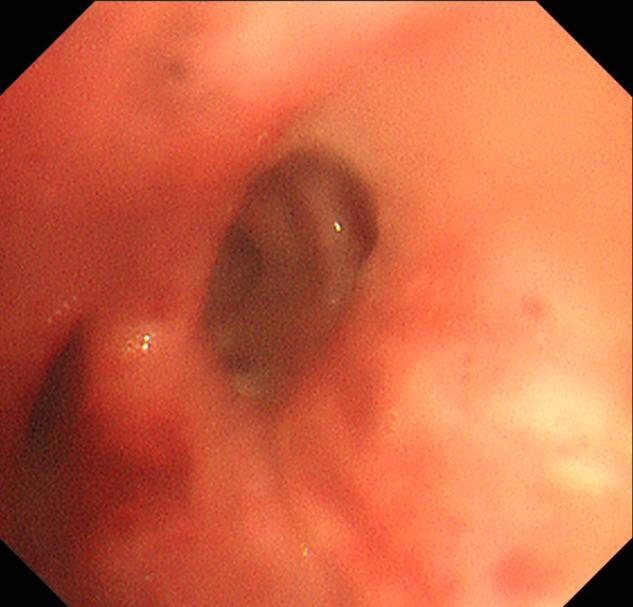

术后患者气道内新生物被完全切除

詹峰当机立断,运用一次性高频电圈套器切除患者气道肿瘤,成功将气道内新生物完全切除。经过内镜复查,患者右侧各段支气管管腔已经恢复了通畅,而且术中出血量极少。手术极大地缓解了患者的病情,改善了她的症状,术后当天,患者咳嗽明显缓解,胸闷感也明显减轻。